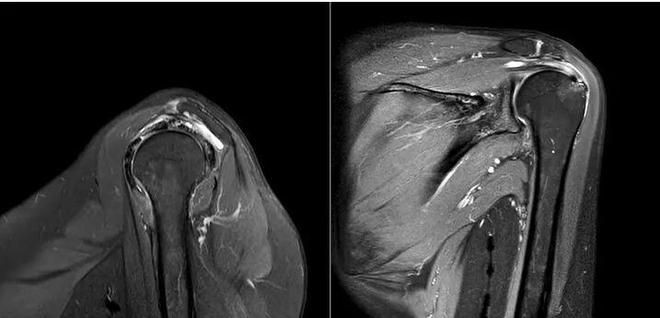

该斜矢状位 MRI 显示冈上肌肌腱部分撕裂;斜冠状位 MRI显示肩峰下滑囊炎改变并积液。